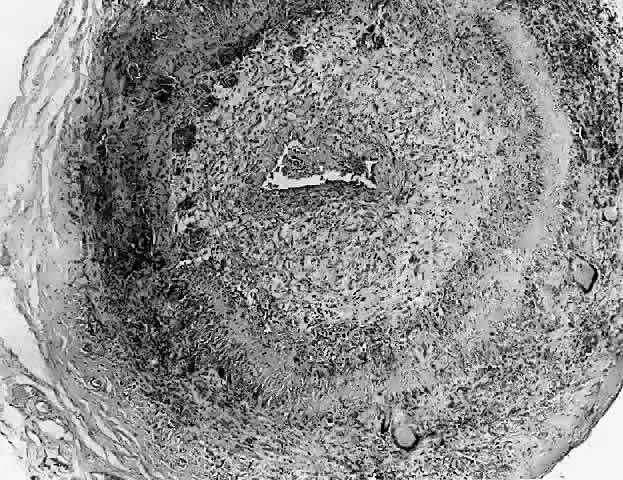

In general, idiopathic orbital inflammation is polymorphic (Figs. 5 AND 6).3,6,7,33,87,88 The cellular response seen in this disease consists of lymphocytes, plasma cells, macrophages, histiocytes, occasional neutrophils and eosinophils, epithelioid cells, and fibroblasts. These are present in varying numbers, depending on the chronicity of the inflammatory process. Intranuclear Dutcher bodies and intracytoplasmic Russell bodies may be present within many of the plasma cells since they actively participate in the inflammatory response. Children tend to have a significant number of eosinophils in their biopsy specimen. Lipogranulomatous inflammation with fat necrosis may also be present. However, the presence of noncaseating granulomas is relatively uncommon.89 This is often associated with foreign body giant cells that are responding to the release of lipid. Perivascular lymphocytic cuffing and capillary proliferation are quite common.3 Occasionally, lymphoid follicles may also be seen.

Fig. 6. Histopathologic sections demonstrating the various pathologic findings associated with idiopathic orbital inflammation. Most commonly these include lymphoid follicles, granulomas, collagen deposition, and a diffuse mixed inflammatory cell infiltrate. The normal tissue architecture is frequently disrupted by these changes. A. Many lymphoid follicles are scattered throughout orbital tissue (H&E, × 63). B. Cells of follicular center are lighter and larger than mantle of mature lymphocytes that surround the germinal zone (H&E, ×160). C. Lacrimal gland elements have undergone atrophy in advanced example of idiopathic dacryoadenitis. Fibrosis and lymphocytes have replaced a considerable amount of gland parenchyma (H&E, ×94). D. Myositis in which lymphocytes are loosely aggregated below center and infiltrate between extraocular muscle fibers (H&E, ×160). E. Cuffing of small vessels by mature lymphocytes. Note loose edematous interstitium between disrupted muscle fibers (H&E, ×240). F. Progressive fibrosis of retrobulbar fat (H&E, ×25).